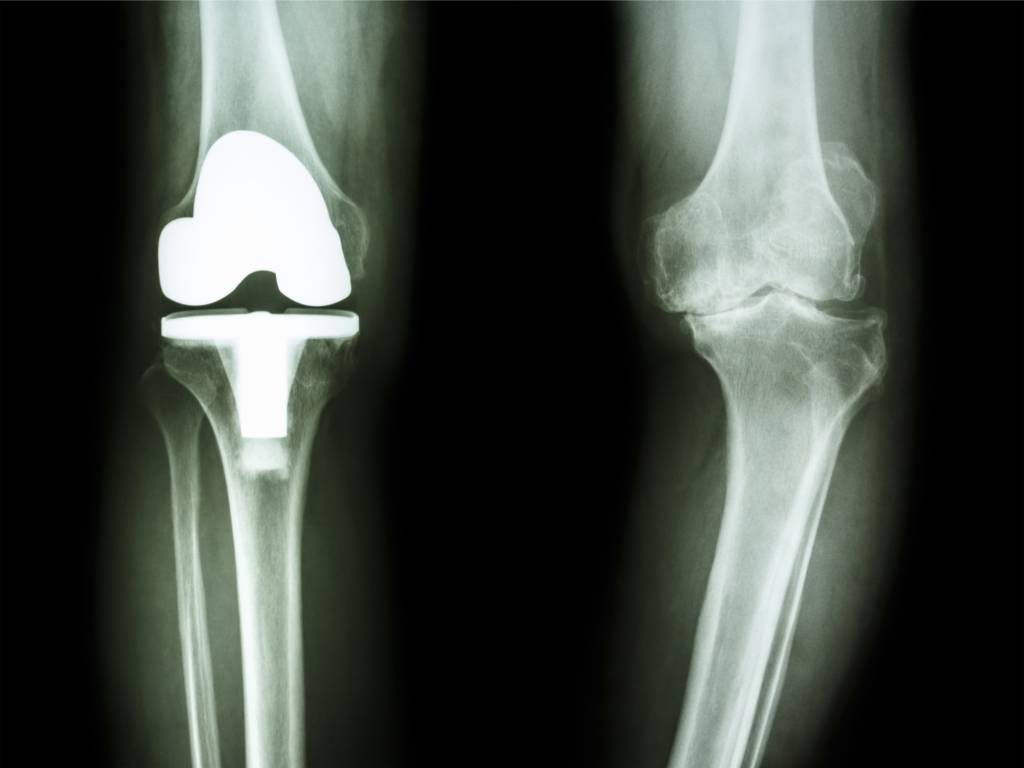

Zum Gelenkersatz gibt es mehrere Prothesenarten von verschiedenen Herstellern. Welche Möglichkeit gewählt wird, hängt von den individuellen Umständen ab, so unter anderem vom Zustand der Gelenkkapsel und der Bänder sowie vom Allgemeinzustand des Patienten. Meist wird eine Total-Endoprothese eingesetzt, bei der die gesamte Verbindung von Oberschenkelknochen und Schienbein erneuert wird (Knie-TEP). Nur manchmal genügt eine Teilprothese.

Falls nur ein bestimmter Bereich des Kniegelenks Schäden aufweist, kann unter Umständen eine Teilprothese (Schlittenprothese) eingesetzt werden. Hierbei wird jeweils nach Entfernen des geschädigten Anteils an dieser Stelle ein oberflächlicher Gelenkflächenersatz eingearbeitet.

Die beschriebenen Prothesen können auf unterschiedliche Art und Weise eingepflanzt werden. Häufig vorgenommen wird eine zementfreie Verankerung, wenn die Prothese passgenau in den Knochen eingefügt wird. Hier dauert die Einheilung mehrere Wochen, da das Knochengewebe um die Prothese, die eine raue Oberfläche besitzt, herum wachsen muss. Möglich ist auch eine Einzementierung der Materialien mit speziellem Kunststoff (so genannter Knochenzement). Dieser verhärtet sich nach der Verarbeitung rasch, so dass das betroffene Bein bald wieder belastet werden kann. Bisweilen kommen beide Varianten an einem Kniegelenk zum Einsatz, wenn an einem Ende eine Einzementierung, am anderen Ende jedoch eine zementfreie Verankerung vorgenommen wird.